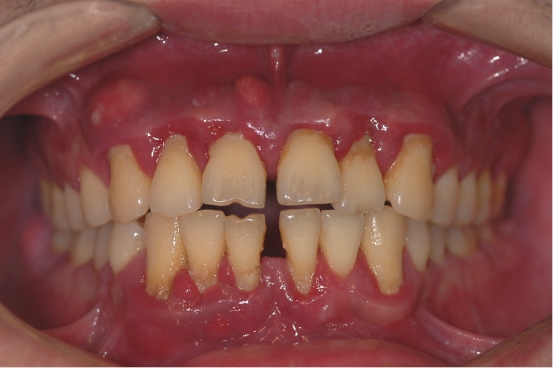

牙缝越来越大,牙齿移位,最后脱落

有的患者发现随着年龄的增长,门牙,尤其是上门牙的牙缝越来越大,牙齿逐渐散开。这是因为我们牙齿的“土壤”即牙槽骨高度越来越低,不足以支撑我们的牙齿,牙齿在很轻的力量的长期作用下,比如说话时舌头作用于牙齿的力就会造成牙齿的移位,导致牙缝越来越大。

食物嵌塞

牙周炎症导致牙龈萎缩、牙缝增大,食物嵌塞也就随之而来。